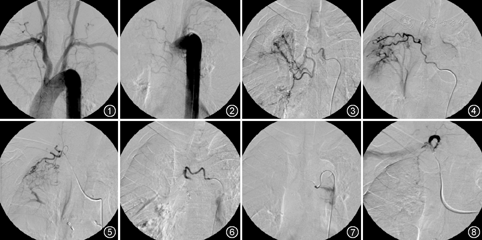

共发现194支病变动脉,其中包括73支支气管动脉,81支肋间动脉,12支胸廓内动脉,16支甲状颈干,12支其他锁骨下动脉分支,表现为病变动脉明显扩张、迂曲,末梢血管丛状紊乱不规则,造影剂外渗,其中可见病变动脉—肺循环瘘115支,表现为病变动脉增粗、扭曲,动脉期临近的肺动、静脉显影(图1,图2,图3,图4,图5)。34例共栓塞193支病变动脉(图6,图7,图8),1例患者因支气管动脉—肺静脉瘘瘘口太大,无合适栓塞材料,未能作栓塞。近期疗效:临床治愈26例,显效3例,有效2例,无效3例(其中死亡1例),总有效率91.2%,治愈率76.5%;术后随访1~2年,临床治愈24例,显效4例,有效1例,无效5例(其中死亡3例,包括术后死亡1例),总有效率85%,治愈率71%。近期无效病例中1例术后因无法控制的大咯血死亡,远期随访1例因肺结核复发再发大咯血,家属拒绝再次介入治疗后死亡,1例因肺结核复发,咯血较前增加,伴发难以控制的肺部感染死亡。部分患者术后有胸骨后灼热感、胸闷、胸痛及肩部疼痛,少数患者发热,严重时予以对症处理后缓解,未出现脊髓损伤及异位栓塞等比较严重的合并症。

肺的体循环是咯血的主要来源[4],病变动脉的主干明显扩张、迂曲成团,末梢血管丛状紊乱不规则,造影剂外渗,也可以表现为病变动脉与肺动脉、静脉直接相通,形成病变动脉—肺循环瘘,使邻近的外周肺动脉及肺静脉显影。由于肺结核供血动脉的多重性,在治疗过程中,应熟悉不同部位的肺结核常见供血动脉的解剖和变异,否则将会遗漏靶血管,造成治疗疗效降低或复发[5]。当结核病灶累及双肺上叶,病灶相邻的锁骨下动脉及腋动脉各分支则很有可能参与出血,累及胸膜则肋间动脉多参与出血。为减少盲目寻找和避免遗漏,可以先行胸主动脉造影[6],因结核病灶多位于两肺上叶,可作主动脉弓造影或双侧锁骨下动脉造影,视病变部位应仔细检查相应的肋间动脉、锁骨下动脉、胸廓内动脉及甲状颈干等,筛选可疑血管,确定病变血管后,视血管开口方向及走行情况,选择Cobra导管、胃左导管或猎人头导管,冒烟或造影观察反流情况,确保导管头稳定地位于靶血管内,必要时选择微导管超选择性插管,避免异位栓塞。本组共发现194支病变动脉,肋间动脉、锁骨下动脉分支所占病例超过60%,伴有病变动脉—肺循环瘘所占比例接近60%,与肺结核致肺毁损且多累及胸膜有关。除1例支气管动脉—肺静脉瘘患者未能栓塞外,其余病例使用明胶海绵颗粒、聚乙烯醇颗粒和弹簧圈栓塞病变血管,近期及远期疗效均较显著,总有效率>85%,治愈率>70%。